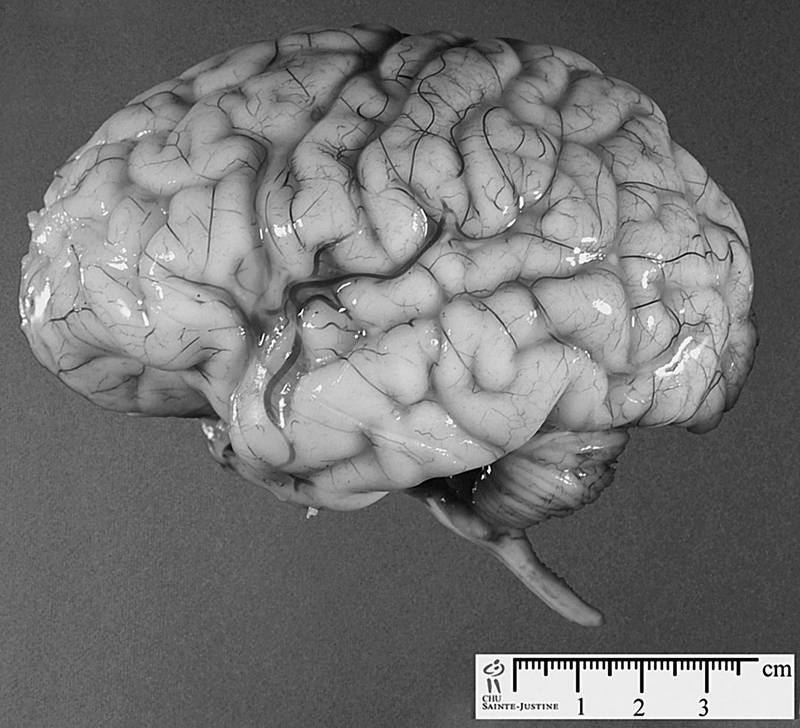

Мозг мужчины отличается от мозга женщины

Немало различий нашли исследователи и в строении мозга мужчин и женщин. Так, мозг мужчины на 150–200 граммов тяжелее женского.